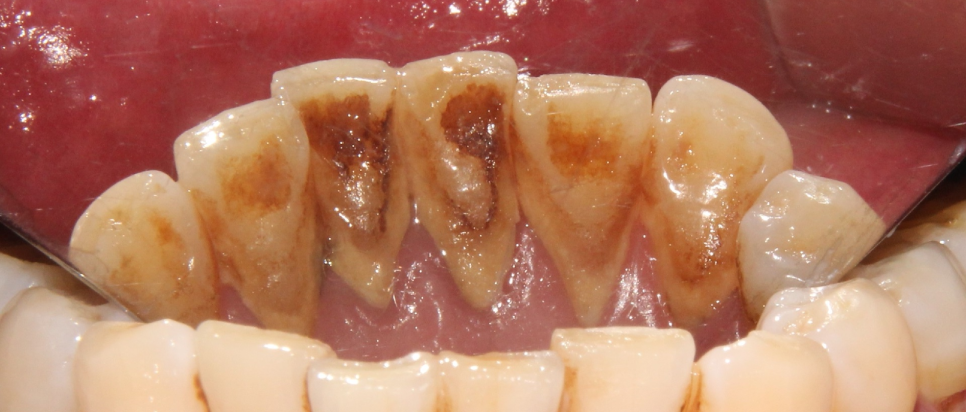

먼저 구내 사진을 보면

치석이 쌓여있고, 착색이 있으며

잇몸이 좋지 못한 모습들이 보여집니다.

치석이 생기는 이유

음식을 먹고 나서 깨끗하게 닦아주지 않아서

치면에 얇은 막이 만들어지고 구강병을 일으키는 세균들이 달라 붙게 되는데

이것을 치태(플라그,plaque) 라 합니다.

치태와 타액 속에 있는 무기질인

칼슘과 인이 만나서

돌처럼 단단하게 만들어져서

쌓이는 것이 치석입니다.

이것은 세균들이 더 번식할 수 있도록 하는

세균들의 집과 같기 때문에

충치와 잇몸질환을 일으키고, 구취가 나게 되며

구강 속 치조골을 점차 녹이게 됩니다.

치태는 잇솔질로 쉽게 제거할 수 있지만

치석은 치아 표면에 붙어있기 때문에

잇솔질로 잘 제거하기가 어렵습니다.

그래서 스케일링을 받아주는 것이 좋습니다.